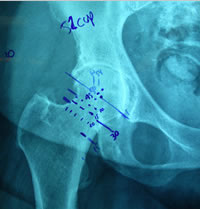

| Pre-op templating |

His own templating process |

Determining neck resection |

Photos from His First Case

Dr. Mackel has participated at cadaver training, observed live surgery and has studied and reviewed the design concept, surgical technique and attended educational seminars prior-to scheduling his first case. It is this dedication to this educational process that reduces his operative learning curve and provides his patients with the best possible clinical/surgical outcome. |

JISRF is pleased that Dr. Mackel has agreed to help define the indications and contraindications on Neck Stabilized Stems for THA and as part of that process, what are the learning curves to preoperative planning (templating). Lateral templating appears to be key in determining stem size and A/P helps to determine level of neck resection (leg length) and femoral offset. |